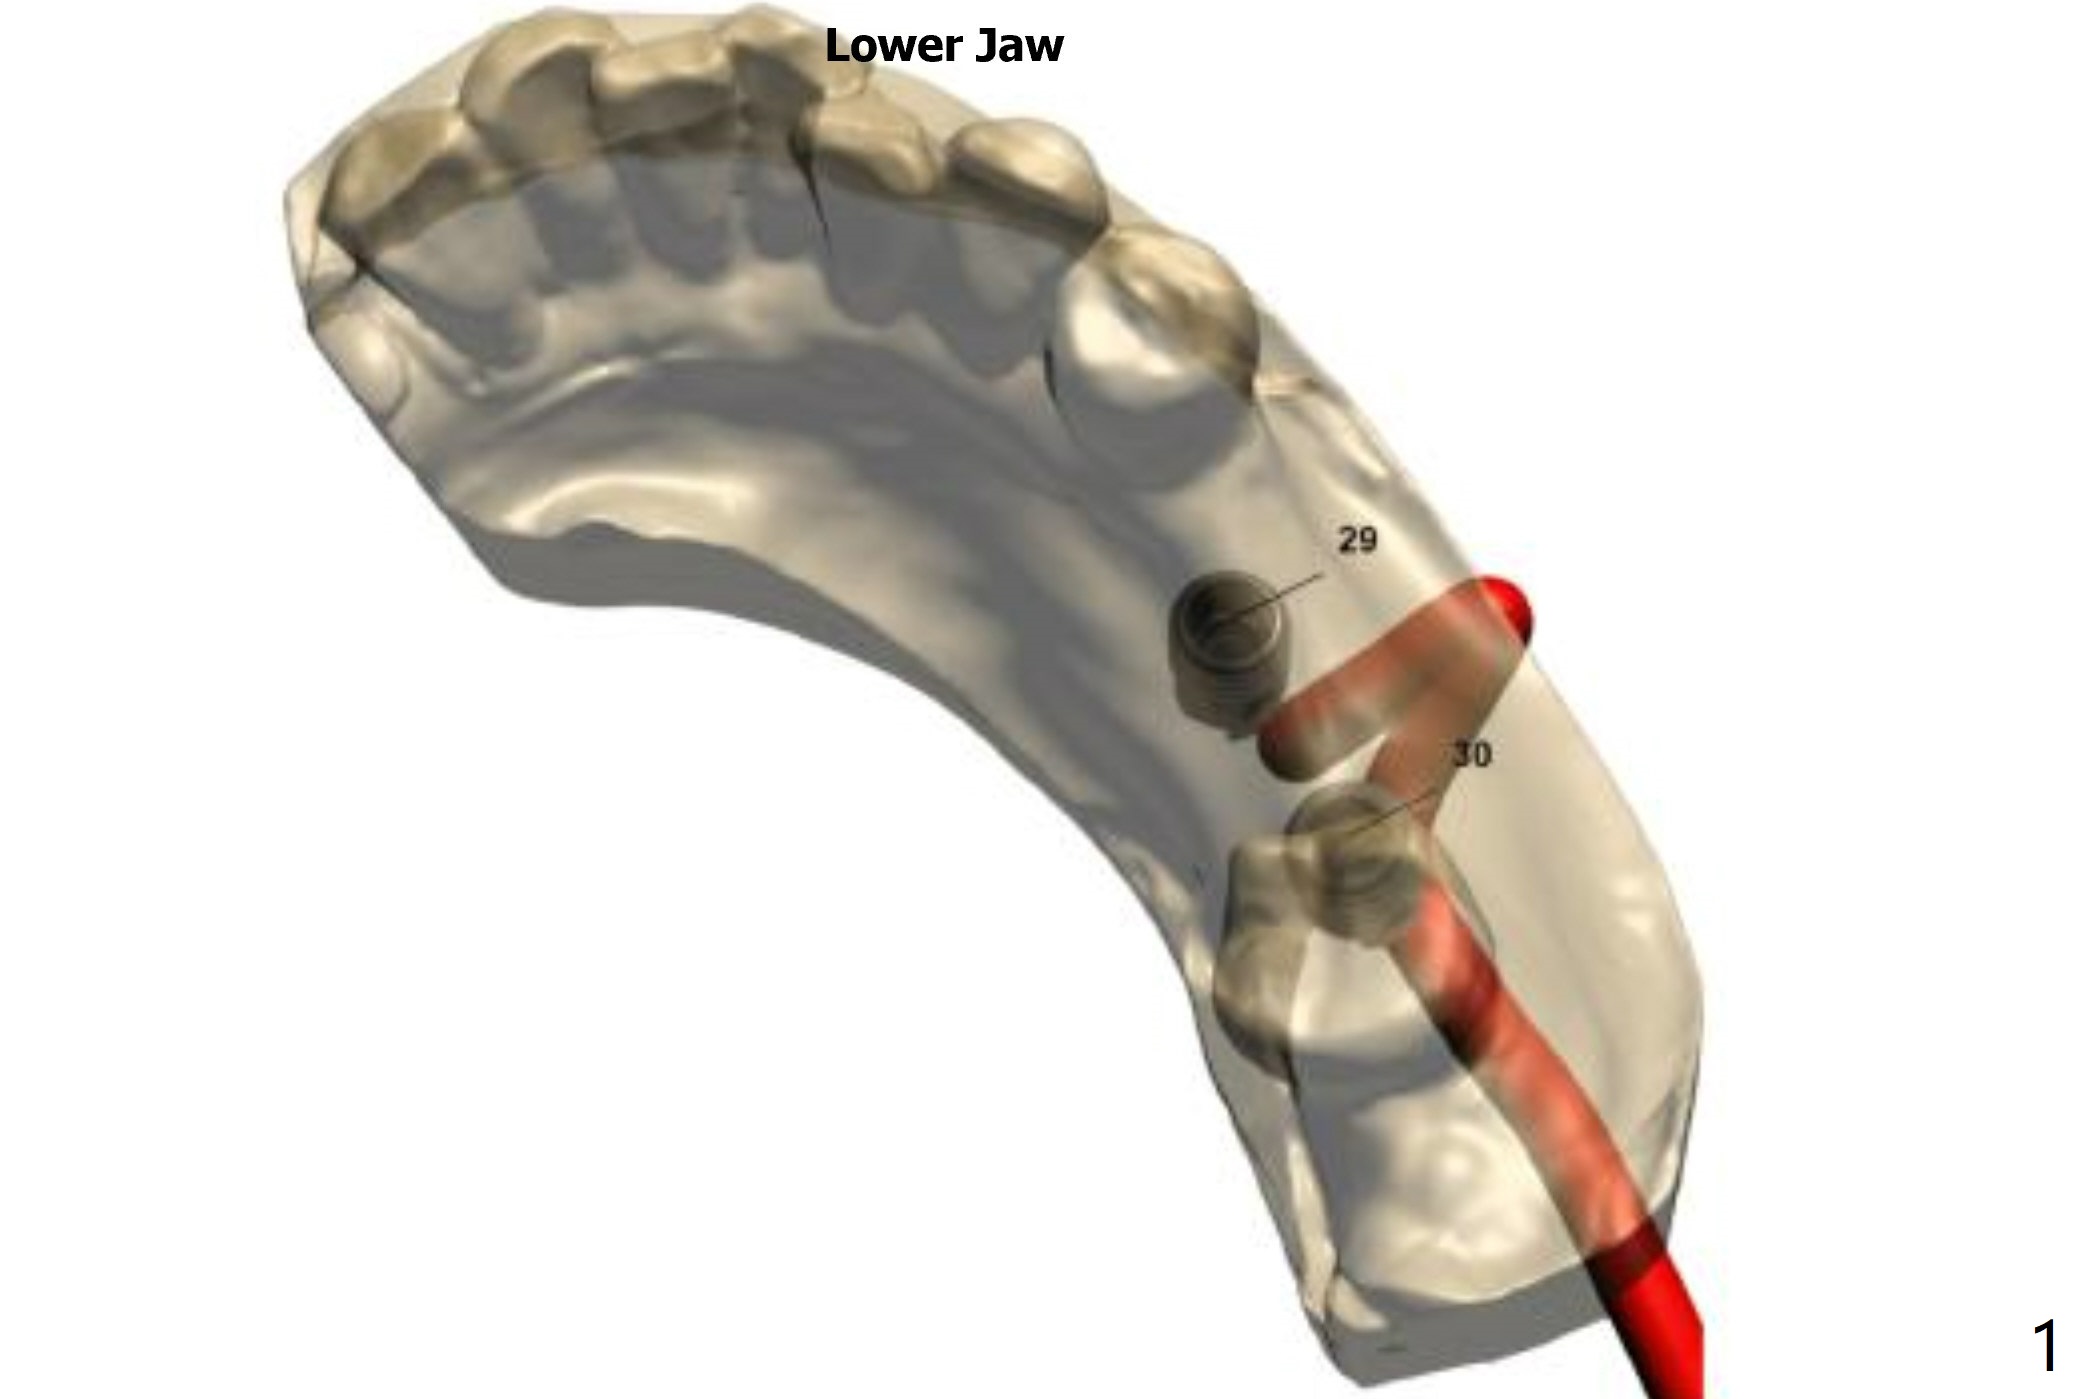

Return to Lower Arch  Molar Premolar  Immediate Implant, Trajectory